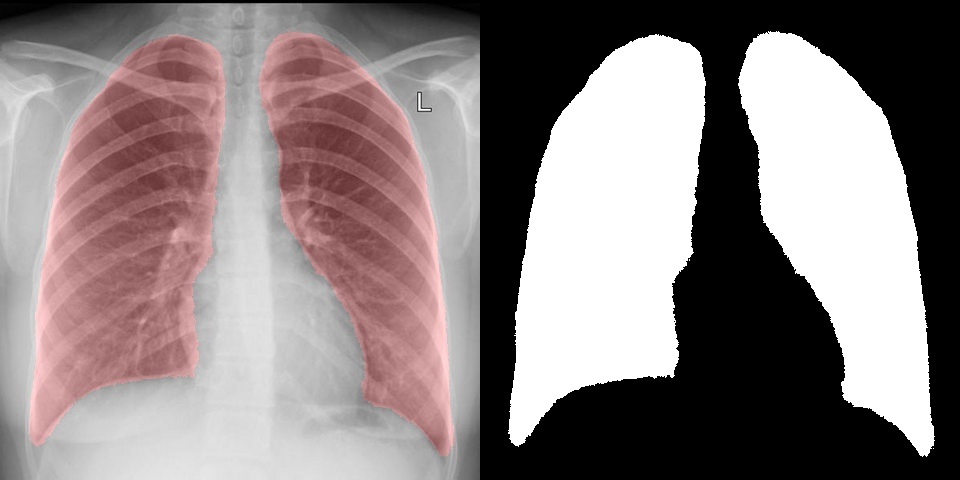

А что если попробовать что-то более необычное, интересное и сложное, например выделение и сегментацию на медицинских изображениях. Для теста снимки флюорографии были взяты с открытой базы КТ и X-RAY снимков, по ним было проведено обучение сегментации легких и в результате удалось достаточно точно выделить интересующую область. На вход сети также подавалось исходное изображение и маска с нулем и единицей. Справа результат, который выдает сверточная сеть, а слева выделена та же область на изображении.

Например, в статье используется модель легких для сегментации. Полученный с помощью сверточных сетей результат нисколько не уступает, а в некоторых случаях даже лучше. При этом, обучить сеть занимает куда быстрее, чем создавать и отлаживать алгоритм.